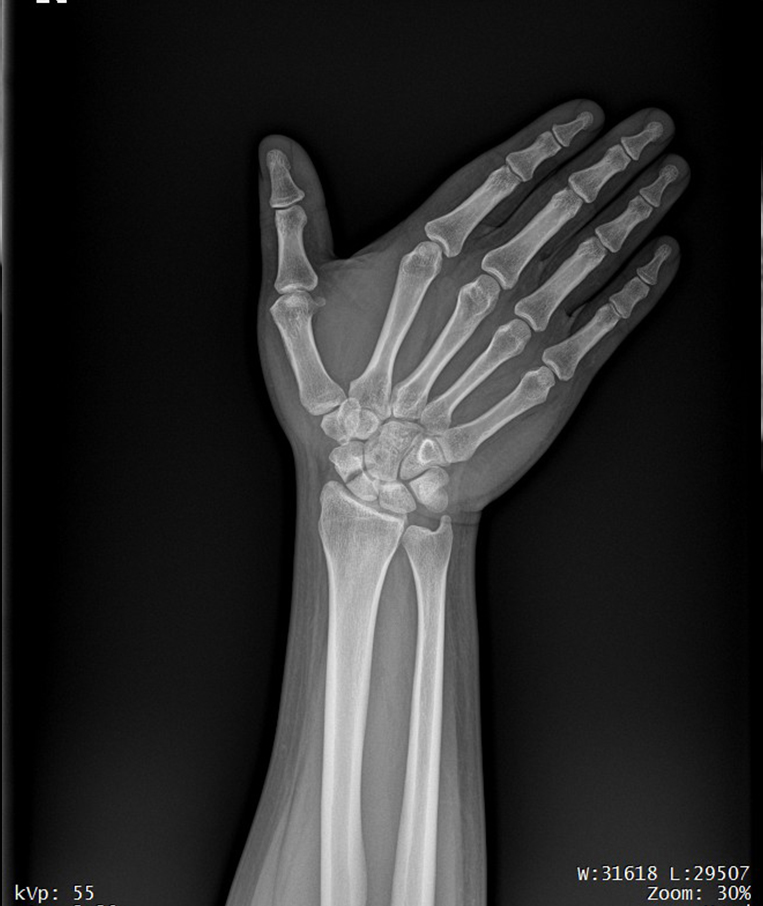

Clinical picture

臨床圖片